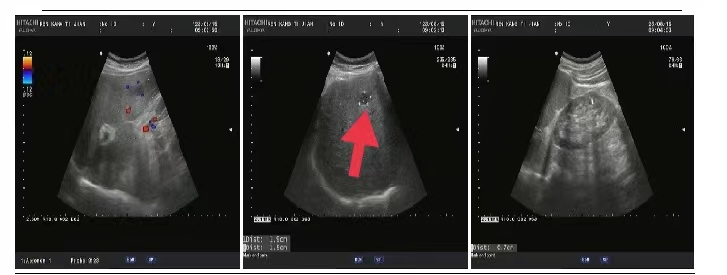

05、**女士,54岁

于2023年8月16日在邯郸仁泰东区体检,膀胱彩超检查提示:膀胱内可见高回声团1.8*1.4cm,边界欠清、形态不规则,内回声不均匀,随体位改变移动不明显。CDFI:周边可见少量血流信号。2023年8月17日首次回访,通知客户到三甲医院进一步检查。2023年8月30日跟踪回访,客户家属告知,在北大医院复查,结果与我院一致,已在北大医院完成手术治疗,现出院在家休养。

06、**男士,65岁

于2023年8月15日在邯郸仁泰北区体检,膀胱彩超检查提示:膀胱充盈尚可,壁不厚,右侧壁见大小约0.6cm*0.4cm稍高回声,边界欠清,形态尚规整,内回声欠均匀,CDFI:未见明显血流信号。尿常规及镜检提示:尿潜血3+,镜检红细胞满视野。当日建议:客户进一步检查。2023年8月31日跟踪回访,客户家属告知,膀胱镜检查诊断为膀胱肿瘤,已住院准备手术。